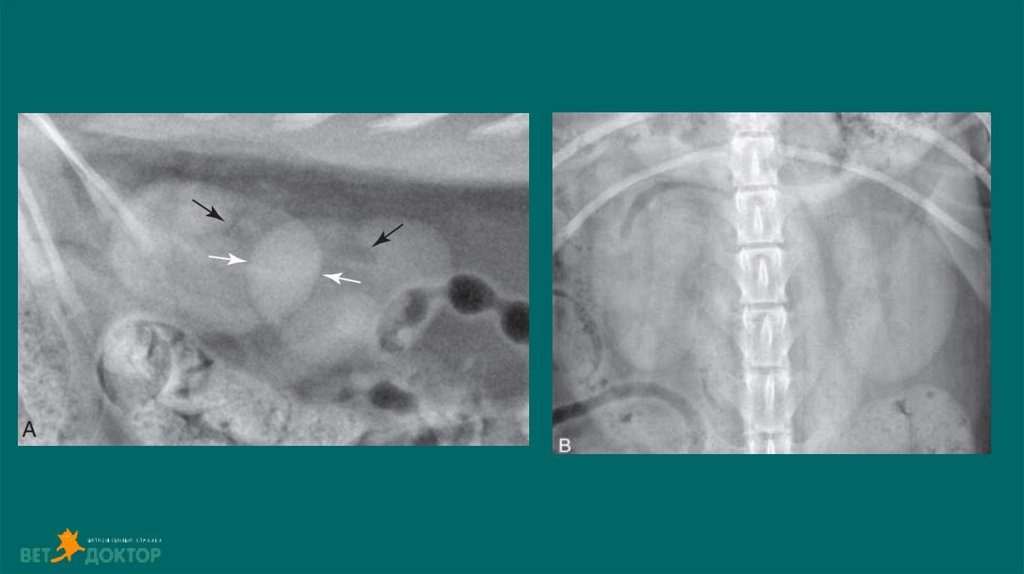

13. Позитивно-контрастная цистоуретрограмма

Показания:

Определение размера, формы и расположения мочевого пузыря

Определение проходимости или разрыва мочевого пузыря или уретры.

Обнаружение дефектов наполнения, связанных с уролитами (цистины/ураты) или гематомами,

выявления полипов или новообразований.

ПОДГОТОВКА

• Установка стерильного мочевого катетера для введения контраста

• Получение обзорных боковых и ВД снимков

• Введение стерильного йодсодержащего контраста в расчете 10мл/кг( разбавлен стерильным

физ.раствором 1:2 или 1:5)

• Выполняем латеральные/ВД снимки немедленно после введения контраста .

• Для получения уретрограммы оттянуть дистально катетер, ввести контраст одновременно сделать

боковой снимок ,провести серию снимков.

• Удаление контраста из мочевого пузыря по завершению